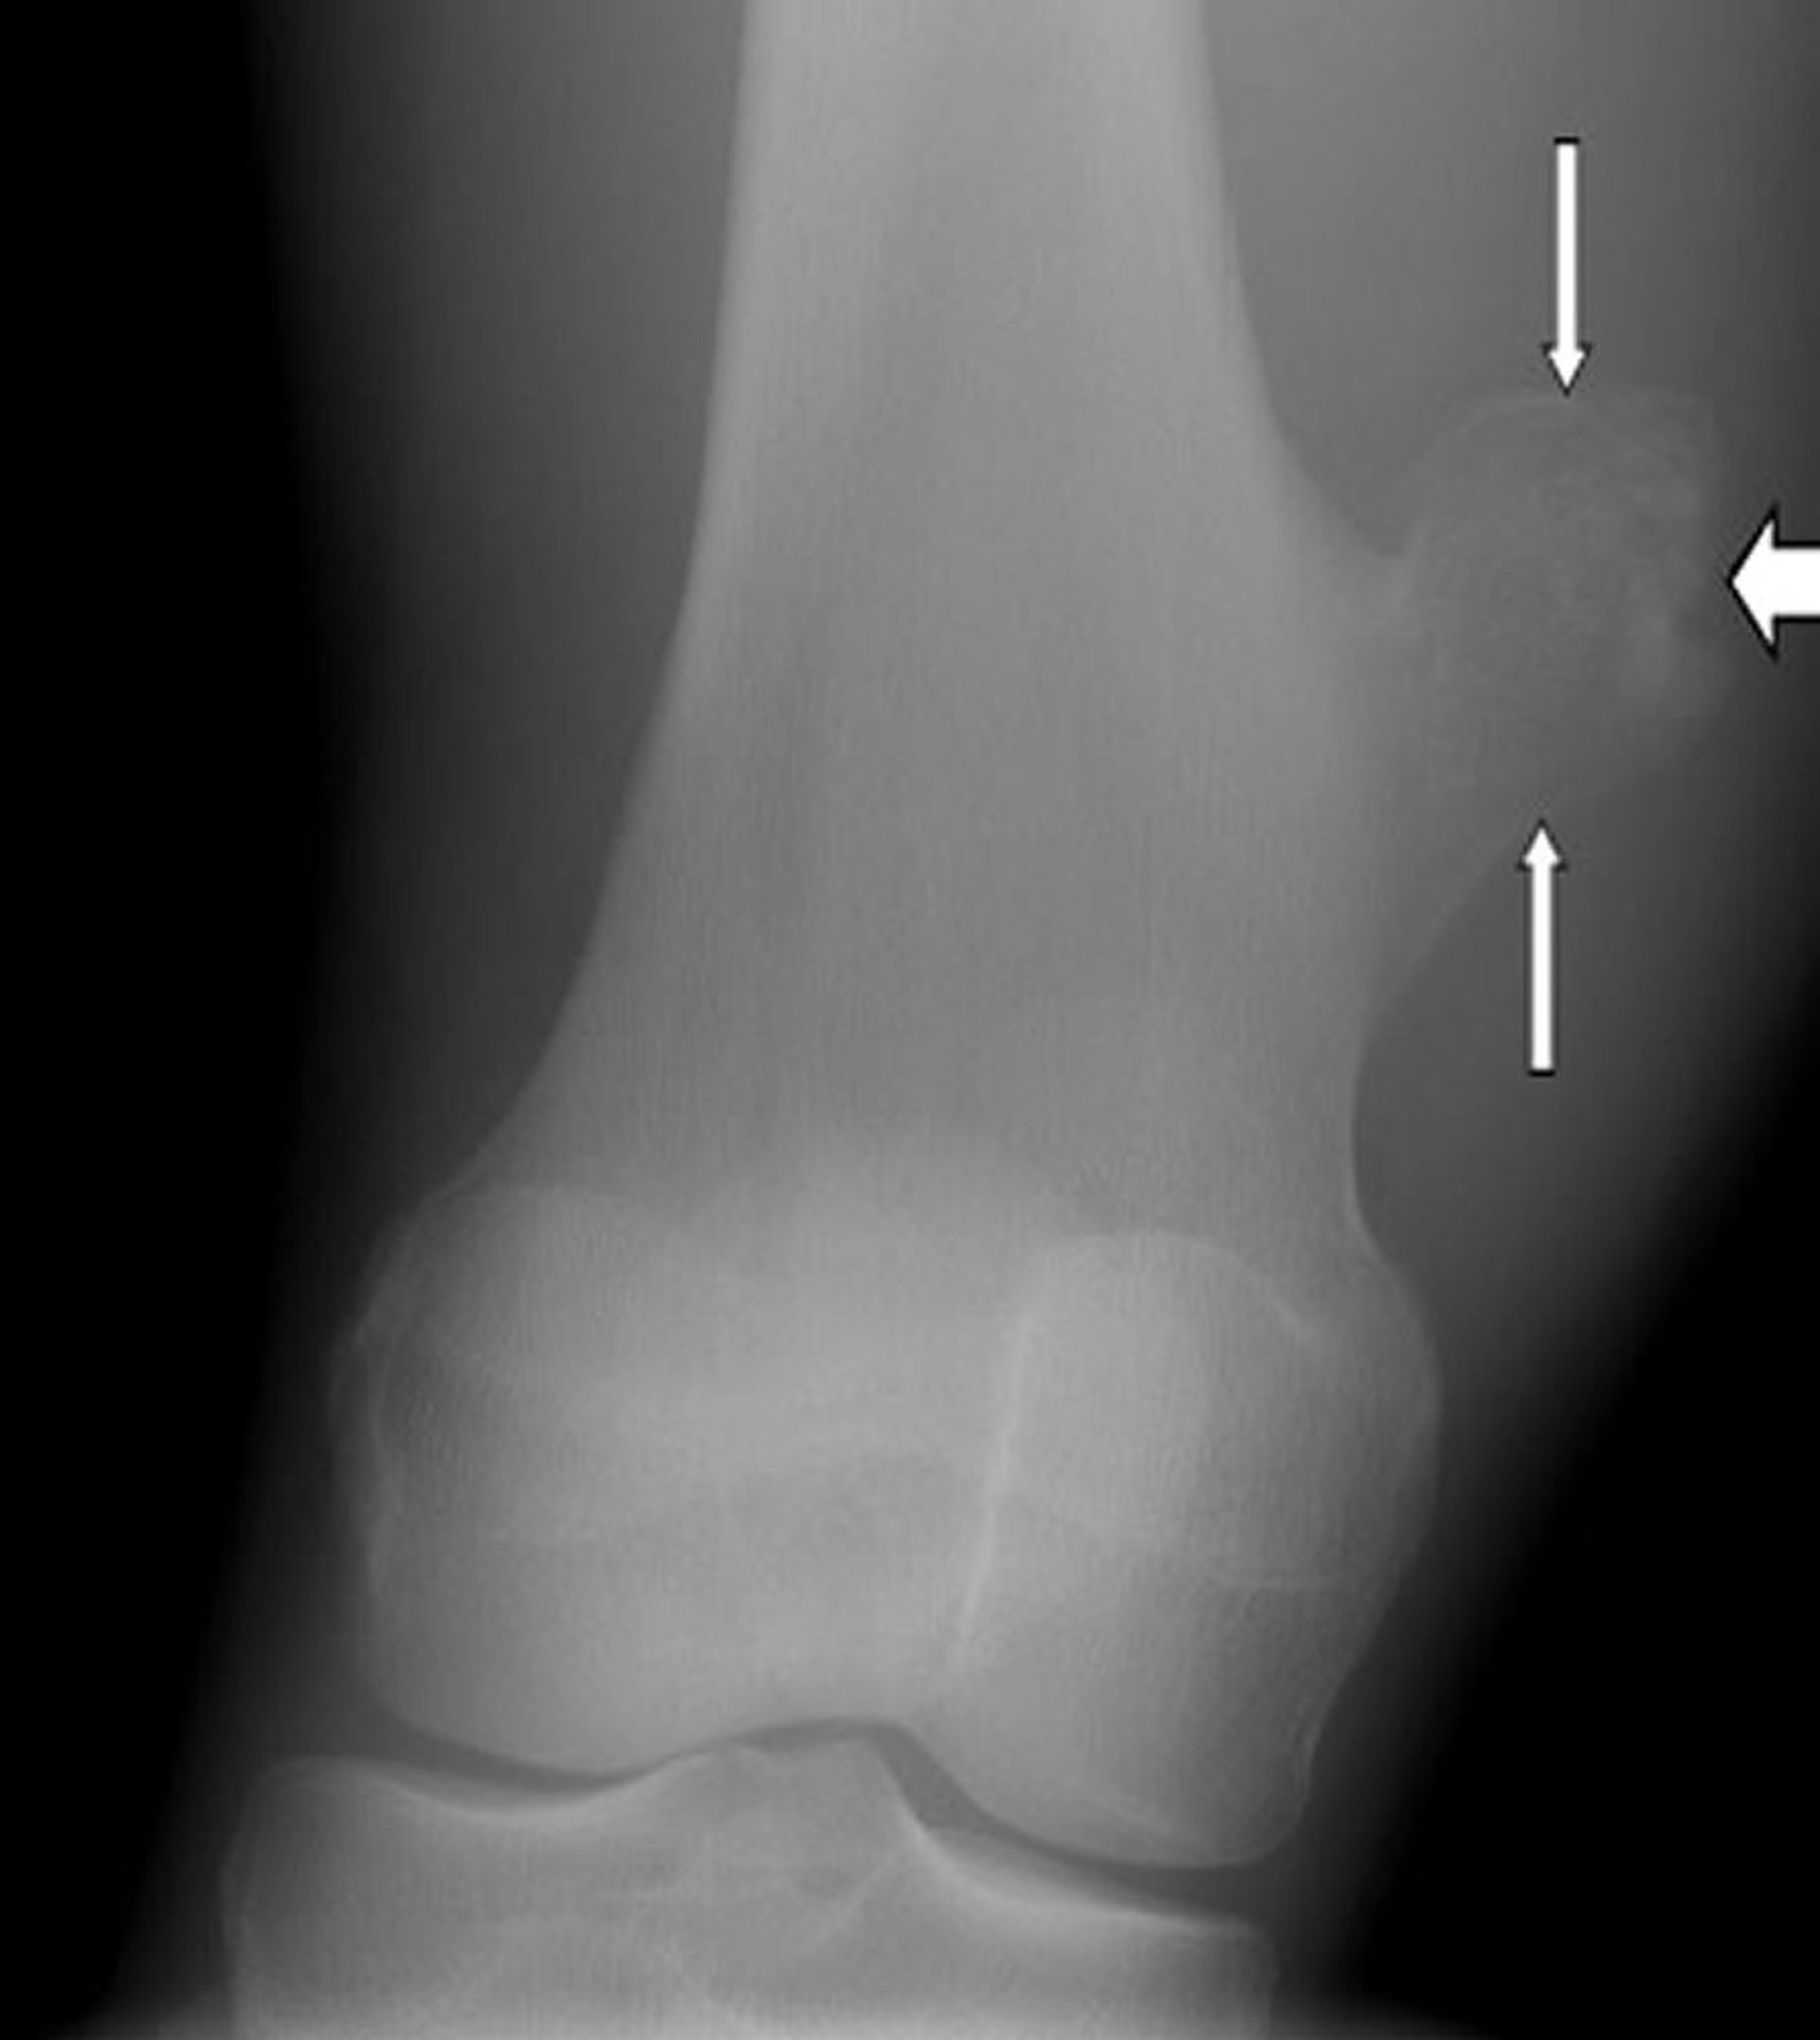

무릎 뼈연골종

이 무릎 X-레이는 무릎 관절 위 허벅지뼈 표면의 성장물(화살표)인 뼈연골종을 보여줍니다.

이미지 제공: Michael J. Joyce, MD 및 Hakan Ilaslan, MD.